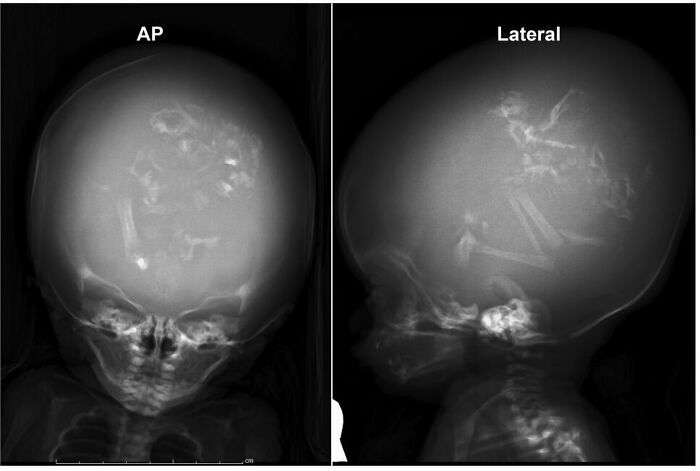

3 Parasitical Twins In The Skull Of A 2 Month Old